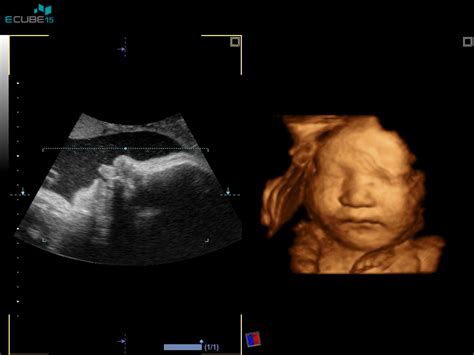

5. Mesec nosečnosti (18. do 21. teden):V sedemnajstem tednu plod je velikosti hruške, dolg 14.5 cm in tehta 110 g. Ušesa so popolnoma formirana, razvija se sluh. Začne se kopičiti maščevje. V osamnajstem tednu plod je dolg 13 cm in tehta 140 g. Srček je popolnoma formiran, plod sliši srčni utrip mame in zvoke iz okolice. V devetnajstem tednu plod je velikosti manga, dolg 17.8 cm in tehta 200 g. Razvija se verniks (beli, mastni premaz), ki ščiti plod. Vsa čutila se intenzivno razvijajo. Lahko se pojavi bolečina krožne vezi, ki podpira maternico. V dvajsetem tednu plod je velikosti banane, dolg 19.7 cm in tehta 260 g. Notranji organi so na svojem mestu. Polovica nosečnosti je mimo, velikost maternice je do popka. Pri okoli 20. tednu se opravi obširnejši ultrazvok, morfologija, kjer ginekolog pregleda razvoj posteljice in otroka. Vidijo se premiki, sliši se bitje srca, pogosto se izve tudi spol otroka.